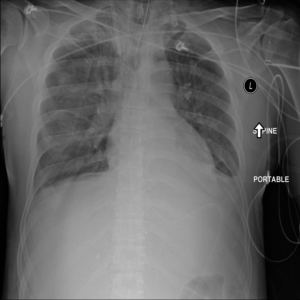

Anomaly detection is the problem of recognizing abnormal inputs based on the seen examples of normal data. Despite recent advances of deep learning in recognizing image anomalies, these methods still prove incapable of handling complex medical images, such as barely visible abnormalities in chest X-rays and metastases in lymph nodes. To address this problem, we introduce a new powerful method of image anomaly detection. It relies on the classical autoencoder approach with a re-designed training pipeline to handle high-resolution, complex images and a robust way of computing an image abnormality score. We revisit the very problem statement of fully unsupervised anomaly detection, where no abnormal examples at all are provided during the model setup. We propose to relax this unrealistic assumption by using a very small number of anomalies of confined variability merely to initiate the search of hyperparameters of the model. We evaluate our solution on natural image datasets with a known benchmark, as well as on two medical datasets containing radiology and digital pathology images. The proposed approach suggests a new strong baseline for image anomaly detection and outperforms state-of-the-art approaches in complex medical image analysis tasks.